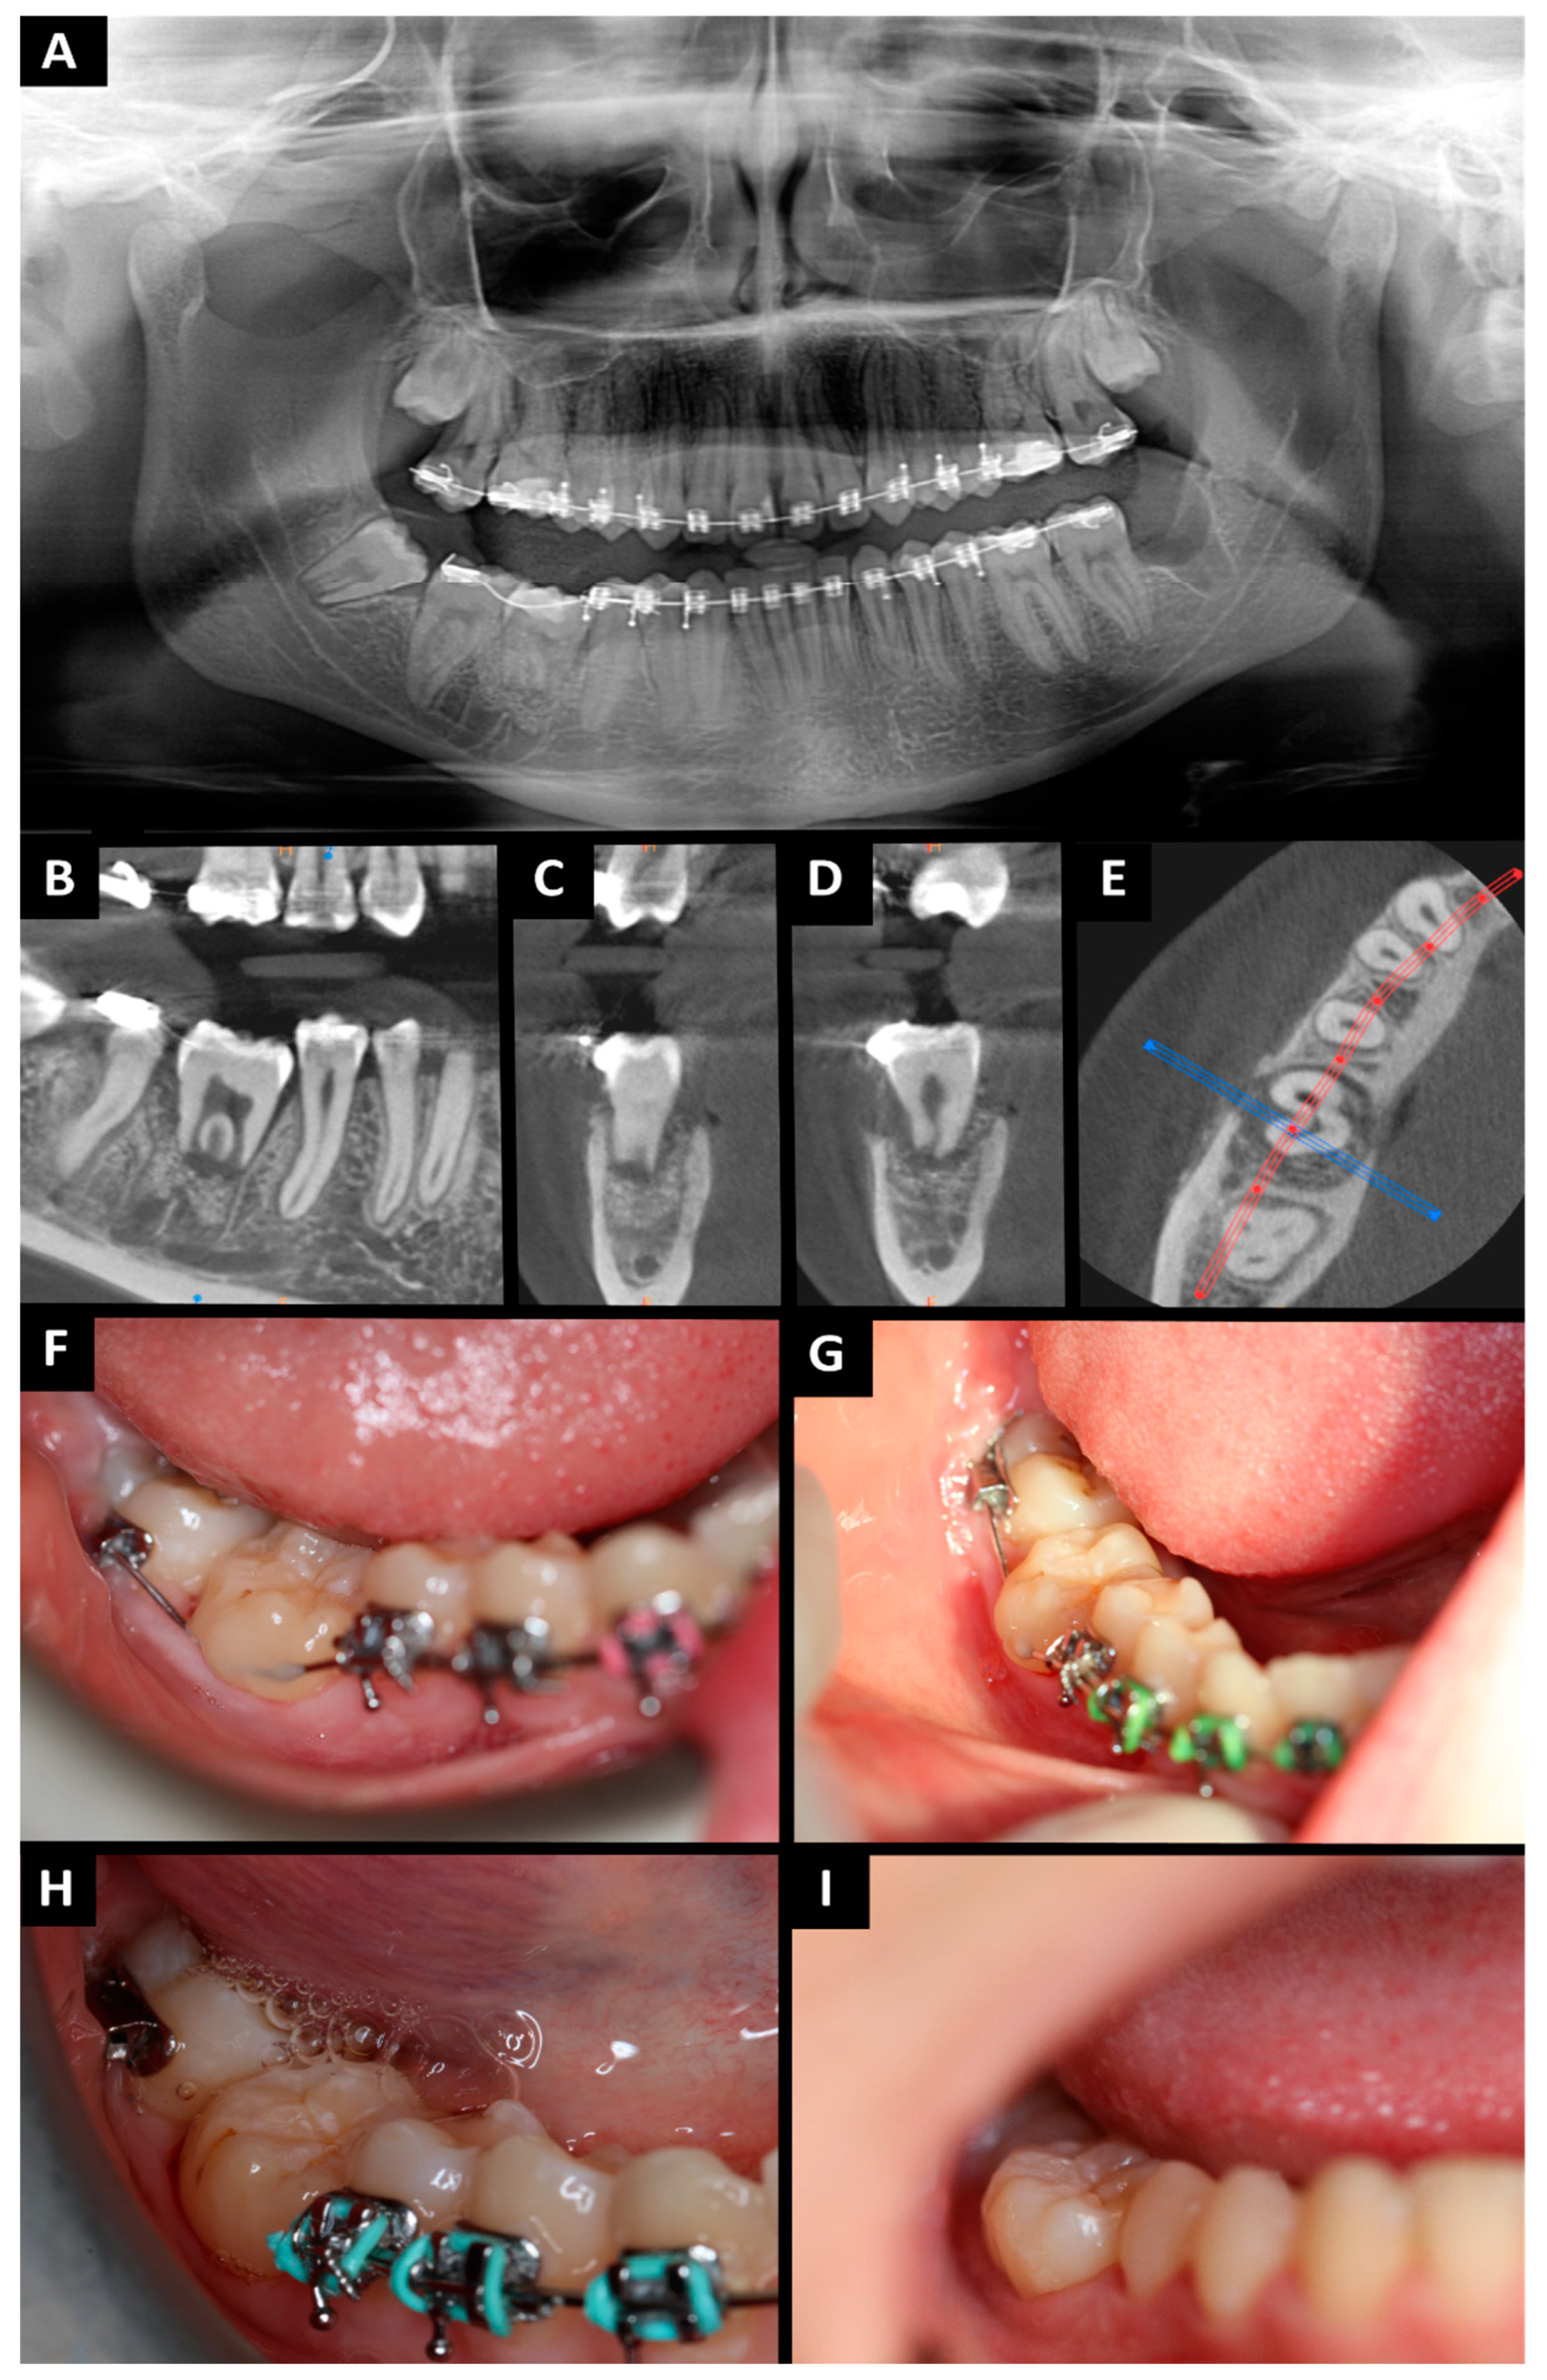

Figure 3.

Orthopantomography (A) tooth no. 38 in place of tooth no. 46 (immediately after surgery); CBCT after 6 weeks (B–D): (B) pantomography reconstruction—tooth no. 38 in place of tooth no. 46; (C) cross-sectional view—mesial root of tooth no. 38; (D) cross-sectional view—distal root of tooth no. 38; (E) axial view—visible bone healing; (F) soft tissue healing after 6 weeks; (G) soft tissue healing after 5 months; (H) intraoral photography after 6 months; (I) intraoral photography after 6 months.

The patient had follow-up visits after 48 h, 7 days, 14 days, 6 weeks, 3 months, 6 months (Figure 3G–I), and 1 year after the procedure (Figure 4). At each visit, the following clinical features were assessed: the sensibility of the pulp on cold stimulus (ethyl chloride) and the depth of gingival pockets. After the surgery, wound healing went well and painlessly. The sutures were removed on day 7. After 14 days and 6 weeks, the condition of the tissues around the transplanted tooth was stable and no inflammation was detected. After three months, there were no signs of inflammation, and the soft tissues were properly healed. The splint was removed. After removing the splint, tooth stability was measured using Periotest (Medizintechnik Gulden e.K., Modautal, Germany; PTV—Periotest value; physiological mobility PTV −08 to +09; I grade of mobility +10 to +19; II grade of mobility +20 to +29; III grade of mobility +30 to +50). The PTV value was +7.1, which corresponds to physiological mobility. Periodontal pocket measurements using the Caroline probe showed the following: mesiobuccal depths of 3 mm, mesiolingual depths of 3 mm, distal–buccal depths of 4 mm, and distal–lingual depths of 4 mm. The pulp sensibility test was not reliable probably due to pulp shock after the procedure. The transplanted tooth was not included in the orthodontic appliance. Six months after the procedure, the patient came for a follow-up visit. The patient did not report any problems in the oral cavity. The intraoral examination showed complete healing of the soft tissue. The pulp sensibility test was inconclusive. The PTV value was +5.8, which is within the limits of physiological mobility. Periodontal pocket measurements showed mesiobuccal depths of 3 mm, mesiolingual depths of 3 mm, distal–buccal depths of 4 mm, and distal–lingual depths of 4 mm.